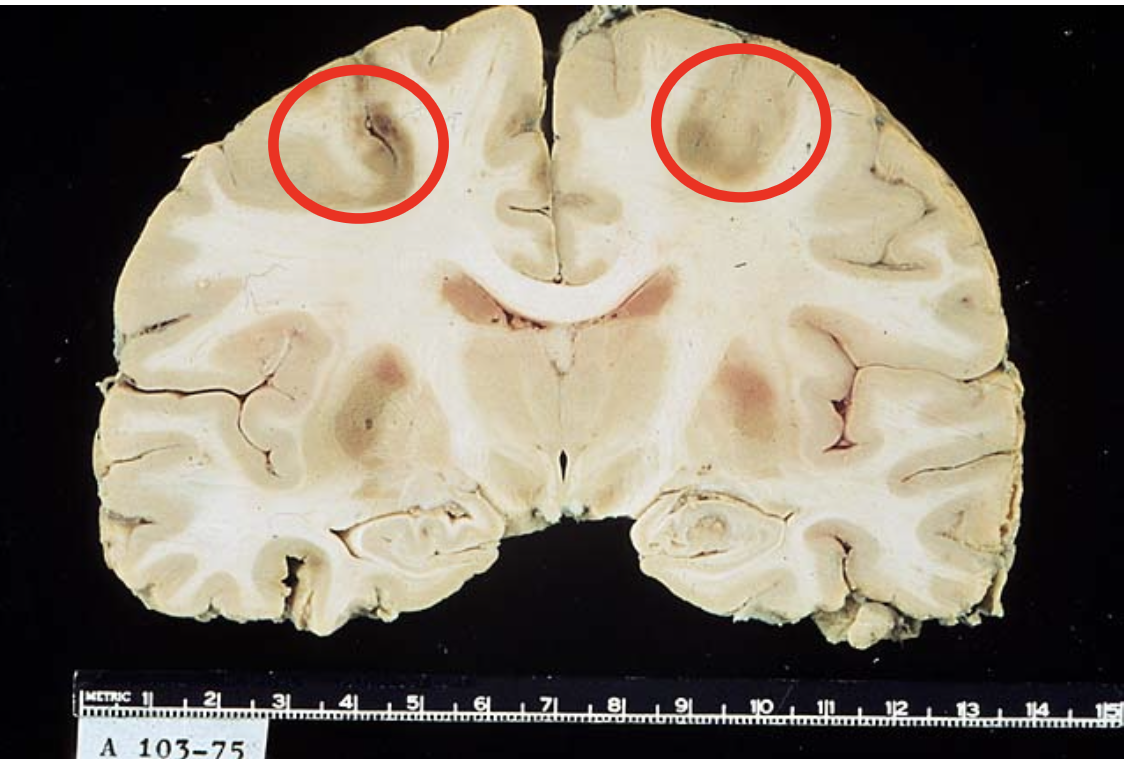

Transient global hypoperfusion - gross

Transient shock or cardiopulmonary arrest causes focal ischemic injury to neurons with high metabolic rates:

– Layer 3 and 5 of cortex (laminar necrosis) (arrow)

– Hippocampus (circle)

– Purkinje cells in Purkinje layer of cerebellum

– Basal ganglia